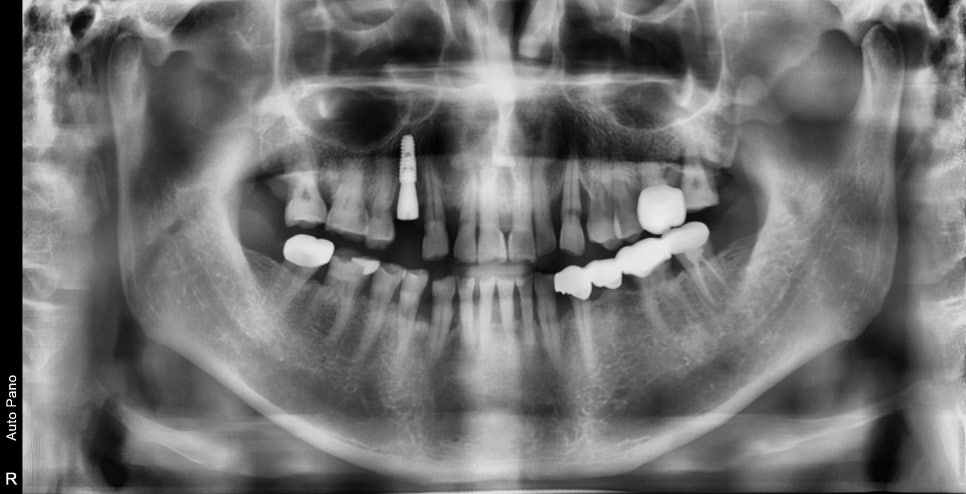

과거에 했던 임플란트 부분이 흔들려서 아파서 씹지도 못해요

엑스레이상 임플란트 주변에 하얗게 보이는

치조골이라는 뼈가 보이지 않고

주변이 새까맣게 보이는 것을 보면 주변 뼈가

임플란트 주위염으로 인해 모두 소실된 것을 볼 수 있습니다.

임플란트의 제거 및 염증조직의 제거

3D CT를 보면 역시나 임플란트가 주변 뼈에 의해

고정을 받고 있지 않았습니다.

치료상 임플란트는 쉽게 제거가 되었고 이미 뿌리 주변에

심한 오염이 진행되어 있었습니다.